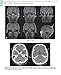

Now presented in full color, this updated edition of Memory Loss, Alzheimer's Disease, and Dementia is designed as a practical guide for clinicians that delivers the latest treatment approaches and research findings for dementia and related illnesses. Drs. Budson and Solomon ― both key leaders in the field ― cover the essentials of physical and cognitive examinations and laboratory and imaging studies, giving you the tools you need to consistently make accurate diagnoses in this rapidly growing area.

- Learn how to use new diagnostic tests, such as the amyloid imaging scans florbetapir (Amyvid), flutemetamol (Vizamyl), and florbetaben (Neuraceq), which can display amyloid plaques in the living brains of patients.